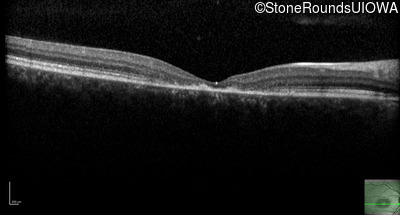

Optical Coherence Tomography - Right - 10/125 -2 sc

Exemplar / OCT Stack

OCT Stack